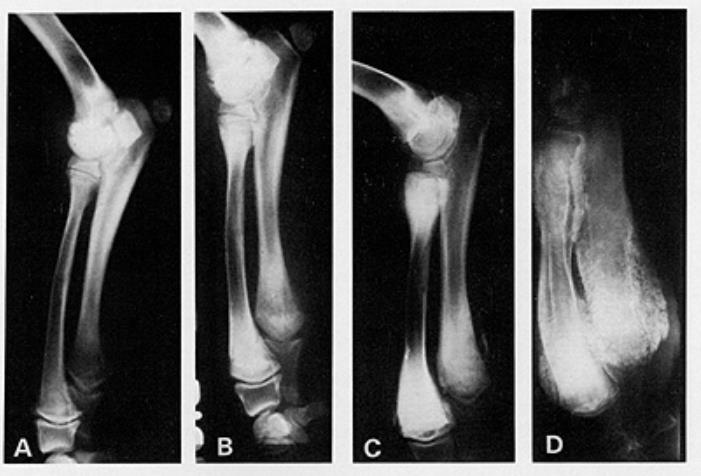

5个月大的肥大性骨营养不良的大丹犬尺骨X光片

X光线通常显示病变骨头的变化,例如与生长板平行线的外观,骨密度的变化以及生长板周围的钙化。